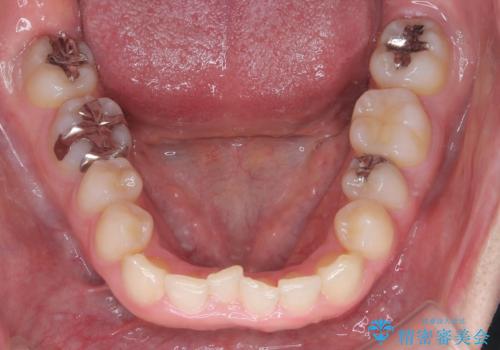

- 下の歯のがたつき(叢生)、真ん中(正中)が右にずれていることを主訴に来院されました。右上前から3番目の永久歯が埋まっている(埋伏)していることから正中は可能な限り合わせることをゴールとしてマウスピースでの矯正治療を選択しました。

今回の矯正治療では、透明なマウスピース型の装置インビザラインを使用しました。がたつきをとるため、安全性が確保できる範囲で歯と歯の間を少し削り必要なスペースを確保しました。